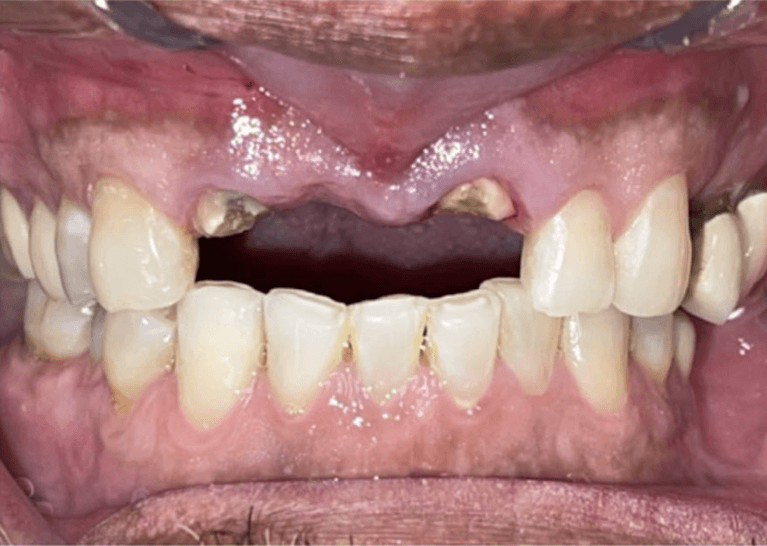

Upper All on 4 fixed implant teeth with Finals. Patient went home with fixed temp teeth the same day.